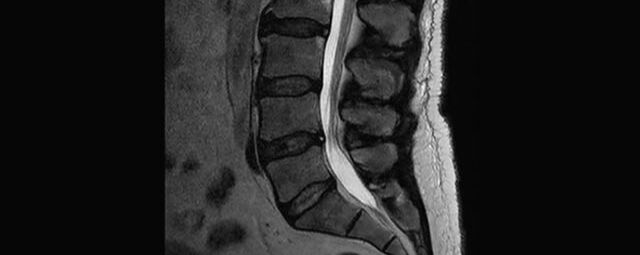

Wirbelsäule

• Abklärung Bandscheibenvorfall

• Beurteilung Einengung des Rückenmarkkanals oder der Neuroforamina im Rahmen der degenerativen Wirbelsäulenerkrankung

• Tumor-/Entzündungsdiagnostik

• Multiple Sklerose

• Abklärung Spondylolisthesis

• Frakturdiagnostik (Alter und Ausdehnung der Fraktur) z.B. im Rahmen der Osteoporose